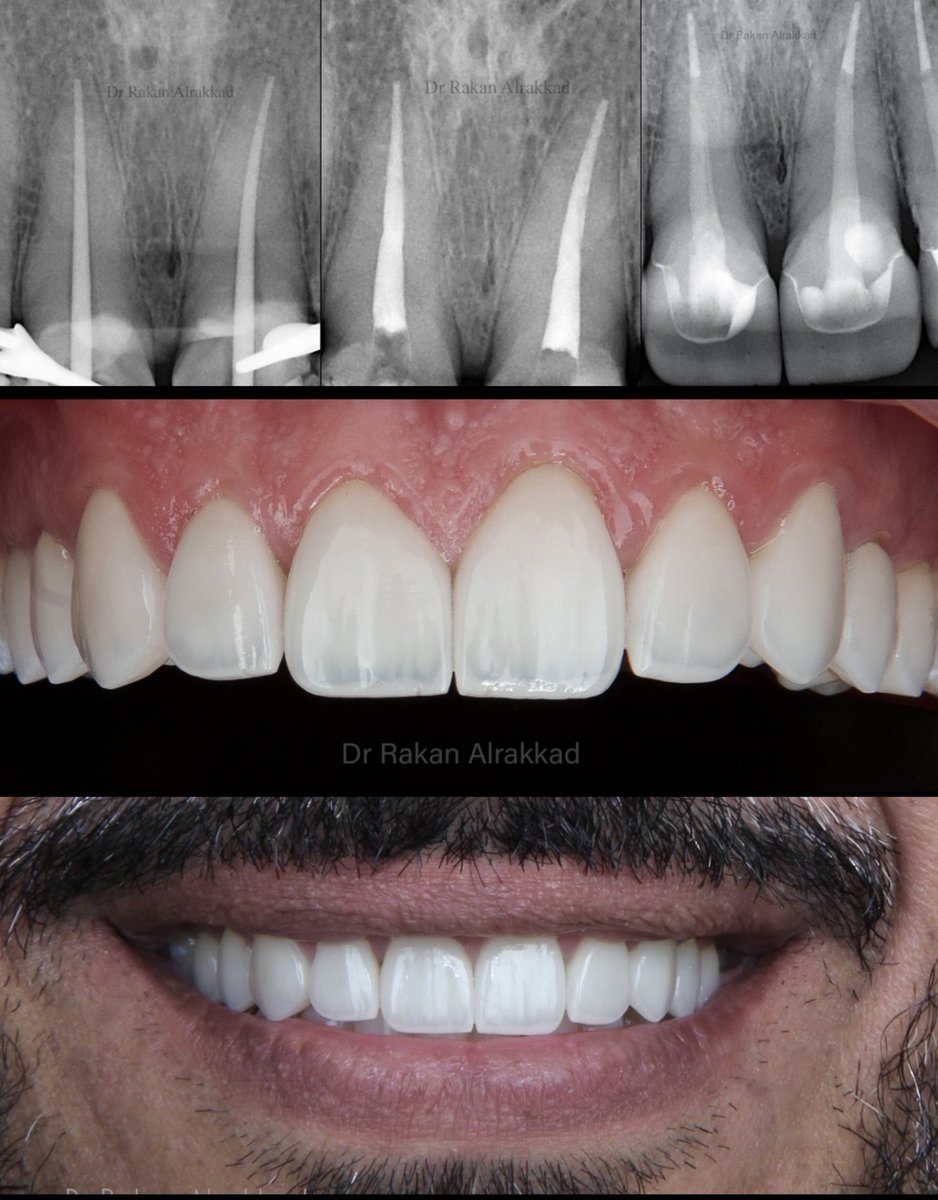

The small detail makes a difference Root canal treatment + post & core E-MAX crowns 👑 All procedures done under rubber dam 🦷

The small detail makes a difference

Root canal treatment + post & core

E-MAX crowns 👑

All procedures done under rubber dam 🦷